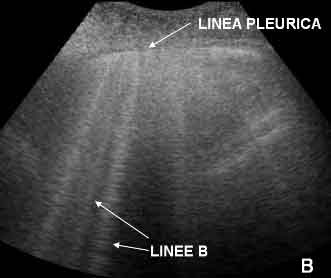

Sono stati inoltre definiti �linee B� degli artefatti verticali normalmente assenti nel polmone normale.

Essi originano dalla linea pleurica, sono ben definiti, raggiungono il margine inferiore dello schermo, mascherano le linee A e si muovono consensualmente all'attivit� respiratoria. La loro presenza nell'adulto identifica una sindrome alveolointerstiziale4 e deriva dalla presenza di setti interlobulari subpleurici pieni di liquido e circondati d'aria.

Poich� il polmone fetale � pi� ricco di liquidi, le linee B sono visibili anche in neonati sani a termine nati sia da parto spontaneo che cesareo. In questo caso per� esse non sono compatte, sono raramente numerose, possono essere visualizzate pi� frequentemente nel polmone destro senza una localizzazione tipica e scompaiono completamente nell'arco di 24-36 ore.

Figura 2. Presenza di artefatti verticali a partenza dalla linea pleurica: linee B.